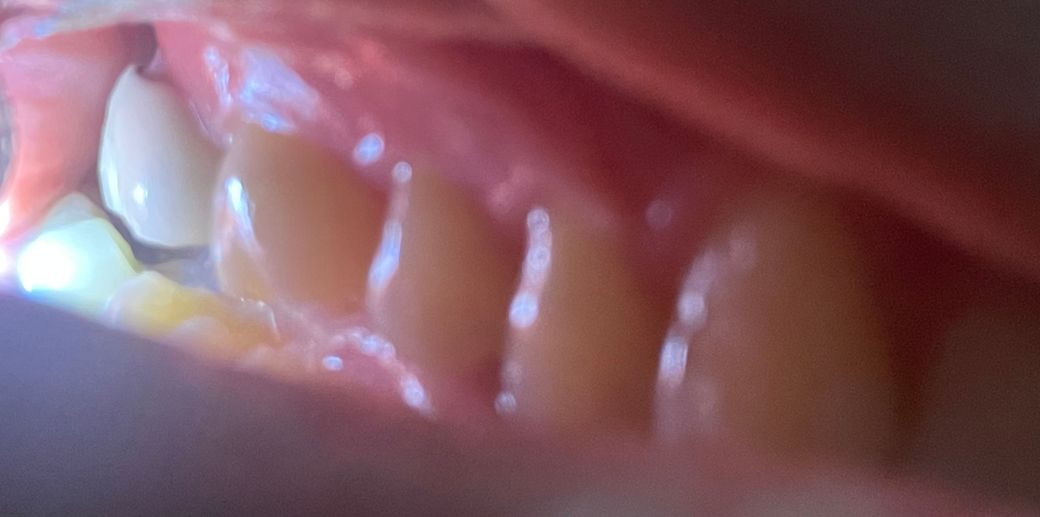

치아사이의 경계면이 마모로 인해서 파인 것으로 보입니다.

마모증은 양치질을 할 때 칫솔을 너무 강하게 움직였을 때 생길 수 있는데 크게 문제가 되지는 않으나 불편감이 있다면 해당 부위를 충전을 하거나 보철물을 다시 제작할 수 있습니다.

현재 상태로서는 해당 보철물을 다시 제작해야 할 수도 있어 보입니다. 치은 연상 마진인지는 현재 사진만으로는 알 수 없고 explorer 등으로 긁어보아야 합니다. gap이 있으므로 치과 방문 후 다시 검사를 해보시는 것이 좋습니다.